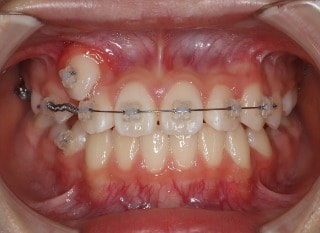

小児期第二段階

開始時

小児期の第二段階

治療中